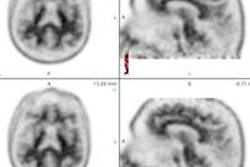

The data are the first published on human use of the agent, added co-author Dr. Manuel Cerqueira from the Cleveland Clinic. "The dynamic aspects of fatty acid imaging are very interesting for the field of cardiac PET," he said.